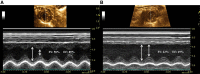

Exercise intolerance is a primary symptom of heart failure (HF); however, the specific contribution of central and peripheral factors to this intolerance is not well described. The hyperbolic relationship between exercise intensity and time to exhaustion (speed-duration relationship) defines exercise tolerance but is underused in HF. We tested the hypotheses that critical speed (CS) would be reduced in HF, resting central functional measurements would correlate with CS, and the greatest HF-induced peripheral dysfunction would occur in more oxidative muscle. Multiple treadmill-constant speed runs to exhaustion were used to quantify CS and D' (distance coverable above CS) in healthy control (Con) and HF rats. Central function was determined via left ventricular (LV) Doppler echocardiography [fractional shortening (FS)] and a micromanometer-tipped catheter [LV end-diastolic pressure (LVEDP)]. Peripheral O2 delivery-to-utilization matching was determined via phosphorescence quenching (interstitial Po2, Po2 is) in the soleus and white gastrocnemius during electrically induced twitch contractions (1 Hz, 8V). CS was lower in HF compared with Con (37 ± 1 vs. 44 ± 1 m/min, P < 0.001), but D' was not different (77 ± 8 vs. 69 ± 13 m, P = 0.6). HF reduced FS (23 ± 2 vs. 47 ± 2%, P < 0.001) and increased LVEDP (15 ± 1 vs. 7 ± 1 mmHg, P < 0.001). CS was related to FS (r = 0.72, P = 0.045) and LVEDP (r = -0.75, P = 0.02) only in HF. HF reduced soleus Po2 is at rest and during contractions (both P < 0.01) but had no effect on white gastrocnemius Po2 is (P > 0.05). We show in HF rats that decrements in central cardiac function relate directly with impaired exercise tolerance (i.e., CS) and that this compromised exercise tolerance is likely due to reduced perfusive and diffusive O2 delivery to oxidative muscles.NEW & NOTEWORTHY We show that critical speed (CS), which defines the upper boundary of sustainable activity, can be resolved in heart failure (HF) animals and is diminished compared with controls. Central cardiac function is strongly related with CS in the HF animals, but not controls. Skeletal muscle O2 delivery-to-utilization dysfunction is evident in the more oxidative, but not glycolytic, muscles of HF rats and is explained, in part, by reduced nitric oxide bioavailability.